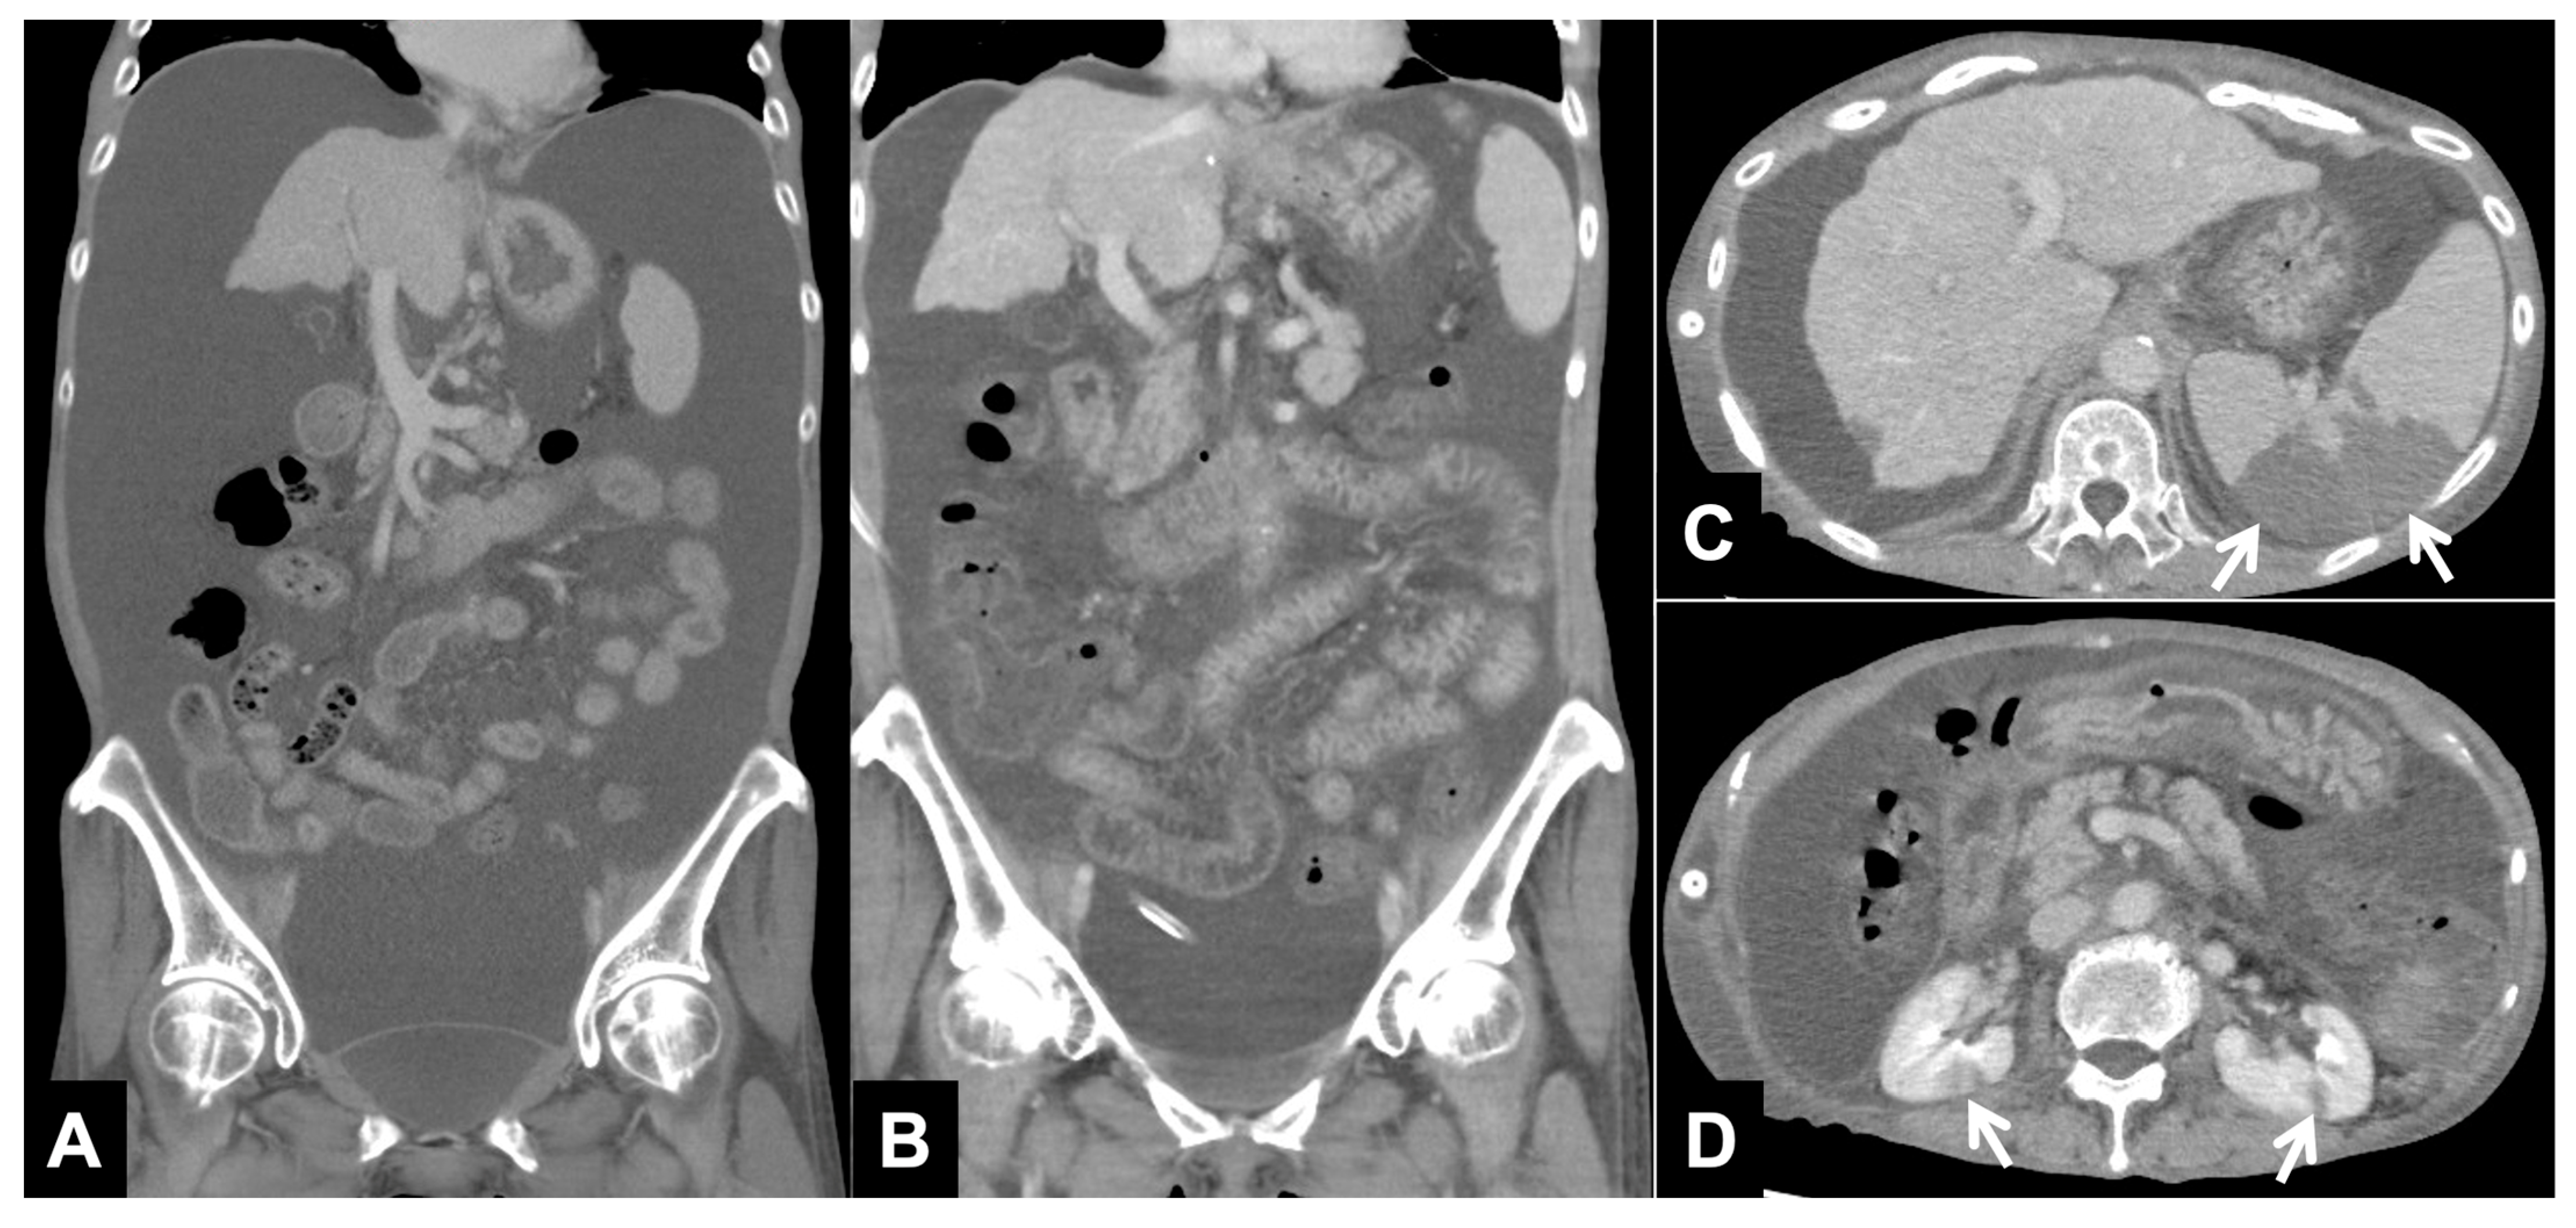

2.4. Chronological Changes of Ascites